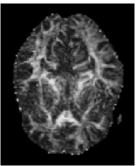

Trace and Mean Diffusivity: The total diffusivity is , and the mean diffusivity (MD) is equal to one third of . The MD measure serves as an indicator of brain maturation and/or injury, and provides the overall magnitude of water diffusion independent of anisotropy [21]. The MD map is shown in Figure 4(c), where higher values of average diffusion appear brighter.

Fractional Anisotropy (FA): FA serves as an indicator of the degree of water diffusion anisotropy independent of the overall water diffusion coefficient and is defined as

| (7) |

which is basically the normalized standard deviation of the eigenvalues. The values of FA vary from 0 to 1 with higher values corresponding to greater diffusion anisotropy. Figure 4(c) shows the FA map of the same slice as in Figure 4(a). The higher values of FA correspond to the WM regions containing densely packed fiber bundles that cause anisotropic diffusion by restricting water movement along the direction perpendicular to the fiber bundles.

![]() |

| (a) | (b) | (c) | (d) |